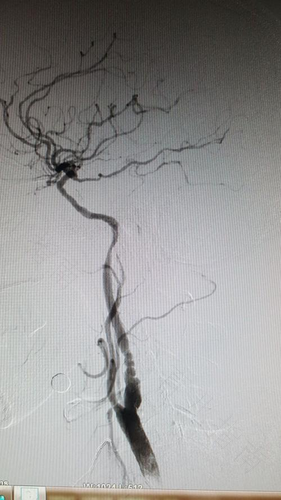

随着生活质量越来越高,食物的种类比以前丰富多了。大鱼大肉以前供应不足,现在每个家庭都可以免费得到。这也导致了一些血管疾病。我们应该理解它们,做好早期预防工作,越早发现它们,治疗它们就越容易。动脉血栓形成的症状是什么?